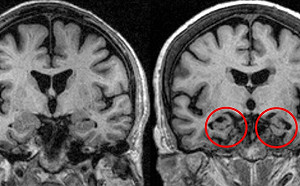

50歲男語言障礙難以表達想法 光田醫:新療法有重大進展